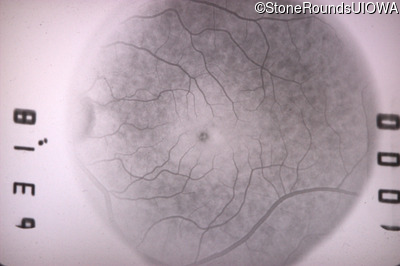

Infrared Fundus Photograph - Left - 20/25

Exemplar